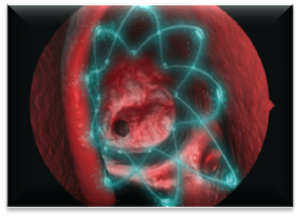

About PROPEL

PROPEL is a relatively new technology that can be used as an adjunt to one of the above procedures. It is clinically proven to improve surgical outcomes for chronic sinusitis sufferers.

When placed in the sinus following surgery, PROPEL decreases scarring and inflammation, reducing the need for additional surgical procedures as well as oral steroids and their potential side effects1.

The spring-like PROPEL implant props open the ethmoid sinus to maintain the surgical opening, delivers an anti-inflammatory medication directly to the sinus lining, and then dissolves, avoiding the need for removal.